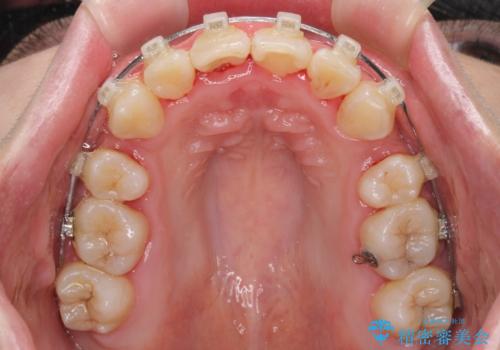

- 骨格的な咬み合わせのズレ、前歯のデコボコとクロスバイトを気にして来院された患者様です。

口元の突出感が若干あり口が閉じにくく、デコボコが強いため、上下左右の小臼歯計4歯を抜歯し、ワイヤー装置による矯正治療を行うこととしました。

治療中に舌の突出癖が改善されず、下顎前歯が著しく前方に突出して反対咬合となってしまう局面がありました。

アンカースクリューを使用しながら舌癖の改善を図り、何とか咬み合わせを改善することができました。